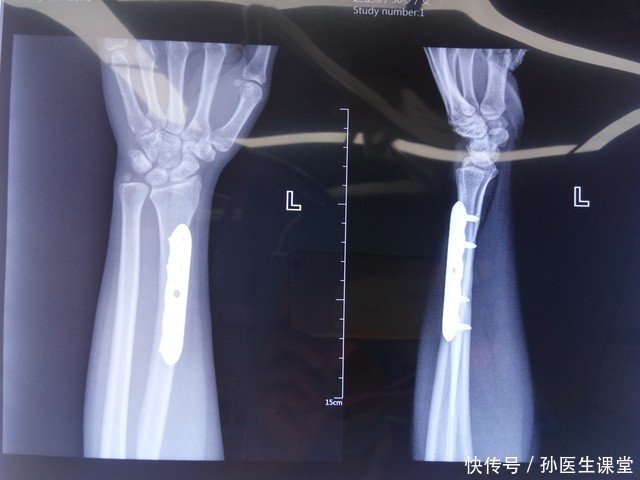

二、轻微外力就容易受伤,骨折或频发骨质疏松使骨骼变得脆弱,即便是平时的小磕碰、轻微摔倒,也可能引发手腕、髋关节或脊椎骨折。临床数据显示,超过60岁的老人,轻微摔倒导致骨折的几率明显上升。一位医生曾比喻:“骨折如同干枯的竹子,稍加弯曲就容易断裂。”当身体出现这种“轻微受力即伤”的迹象时,应当提高警惕,及时做骨密度检查,并在医生指导下采取干预措施。